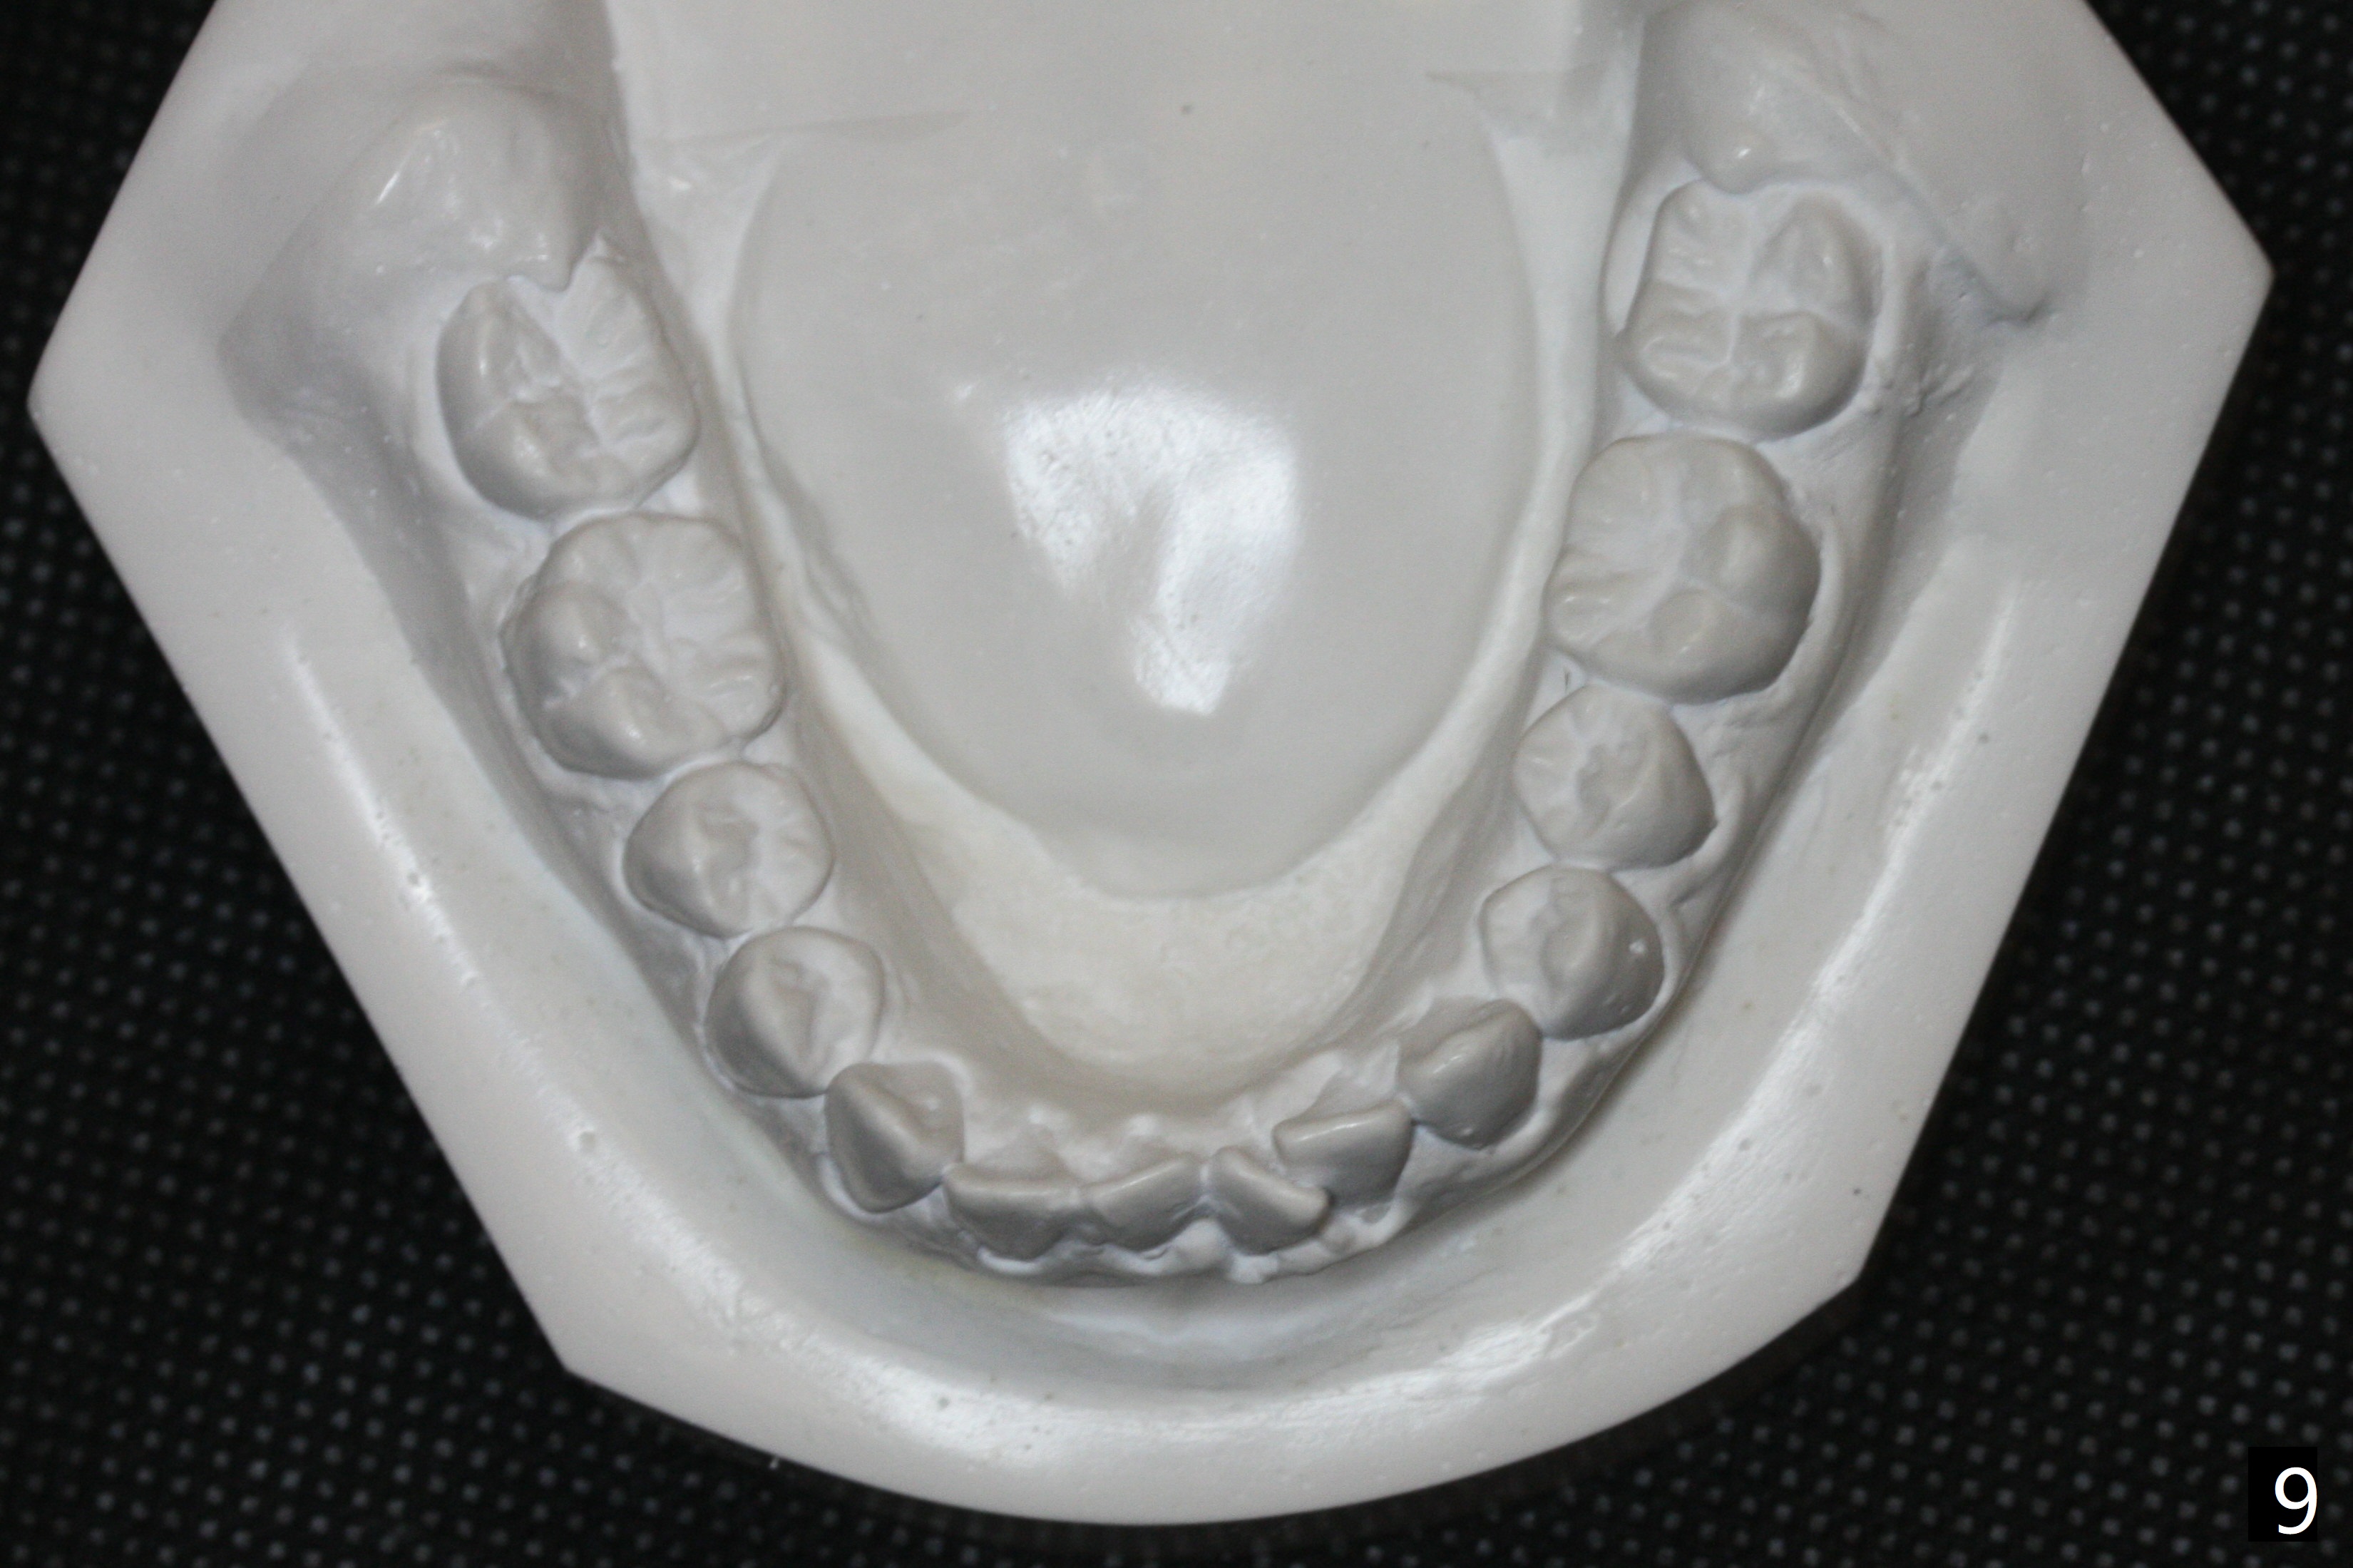

Ten days later UL2 returns to normal position (Fig.6). UR2 is slightly distally displaced; after removal of the rotation wedge at UR1, the same .014' niti wire is re-used (Fig.4). It is expected that UR2 should be able to return to normal position next visit. The wire engagement improves at LR1 (Fig.5). To facilitate LL1 wire engagement, power chain is placed between LL 1 and 3.